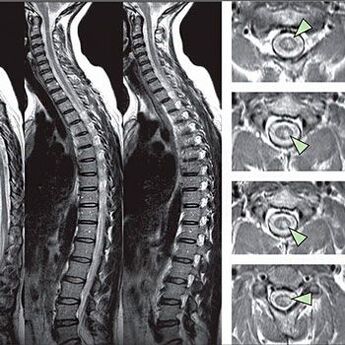

Afin d'identifier les signes de troubles de sensibilité, des tests fonctionnels spéciaux sont effectués. L'option la plus informative de diagnostic à partir des méthodes instrumentales est la performance d'une rayon x. Cependant, pour une étude approfondie de la colonne vertébrale, l'IRM et la TDM sont souvent réalisées. En cas de suspicion de maladies du système cardiovasculaire, le patient est recommandé de subir la procédure ECG.